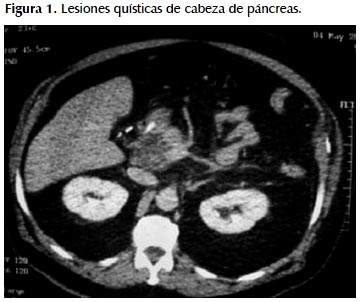

Refiere tener sobrepeso (peso al ingreso 125 kg), consumo discreto de licor, fumador hasta hace 15 años de manera moderada. Antecedentes de hipertensión arterial tratado con Losartán y Amlodipino. Diabetes Mellitus tipo 2 recibiendo Metformina. Litiasis ureteral bilateral, 2007. Colecistectomía laparoscópica 2009. Pancreatitis aguda Balthazar E con pseudoquiste en 1999. Pancreatitis aguda Balthazar E 2003. Pancreatitis aguda Balthazar D en mayo 2010 con re-hospitalización junio 2010 por reagudización del cuadro; la resonancia magnética muestra lesión quística multitabicada en cabeza de páncreas. Ver Figuras 1 y 2.

Por el hallazgo previo de lesión quística se decidió realizar una nueva colangiopancreatografía por resonancia magnética la que mostró crecimiento de un proceso quístico multitabicado y multilobulado, de contornos definidos, que no se asocia a componente sólido o captación patológica de sustancia de contraste, localizado en el proceso uncinado de páncreas, de 4,7x3,9x5,7 cm (Figura 3), y que muestra un conducto único que se comunica con el conducto pancreático principal; se asocia a parénquima pancreático de caracteres normales sin otras lesiones focales en el resto del mismo.